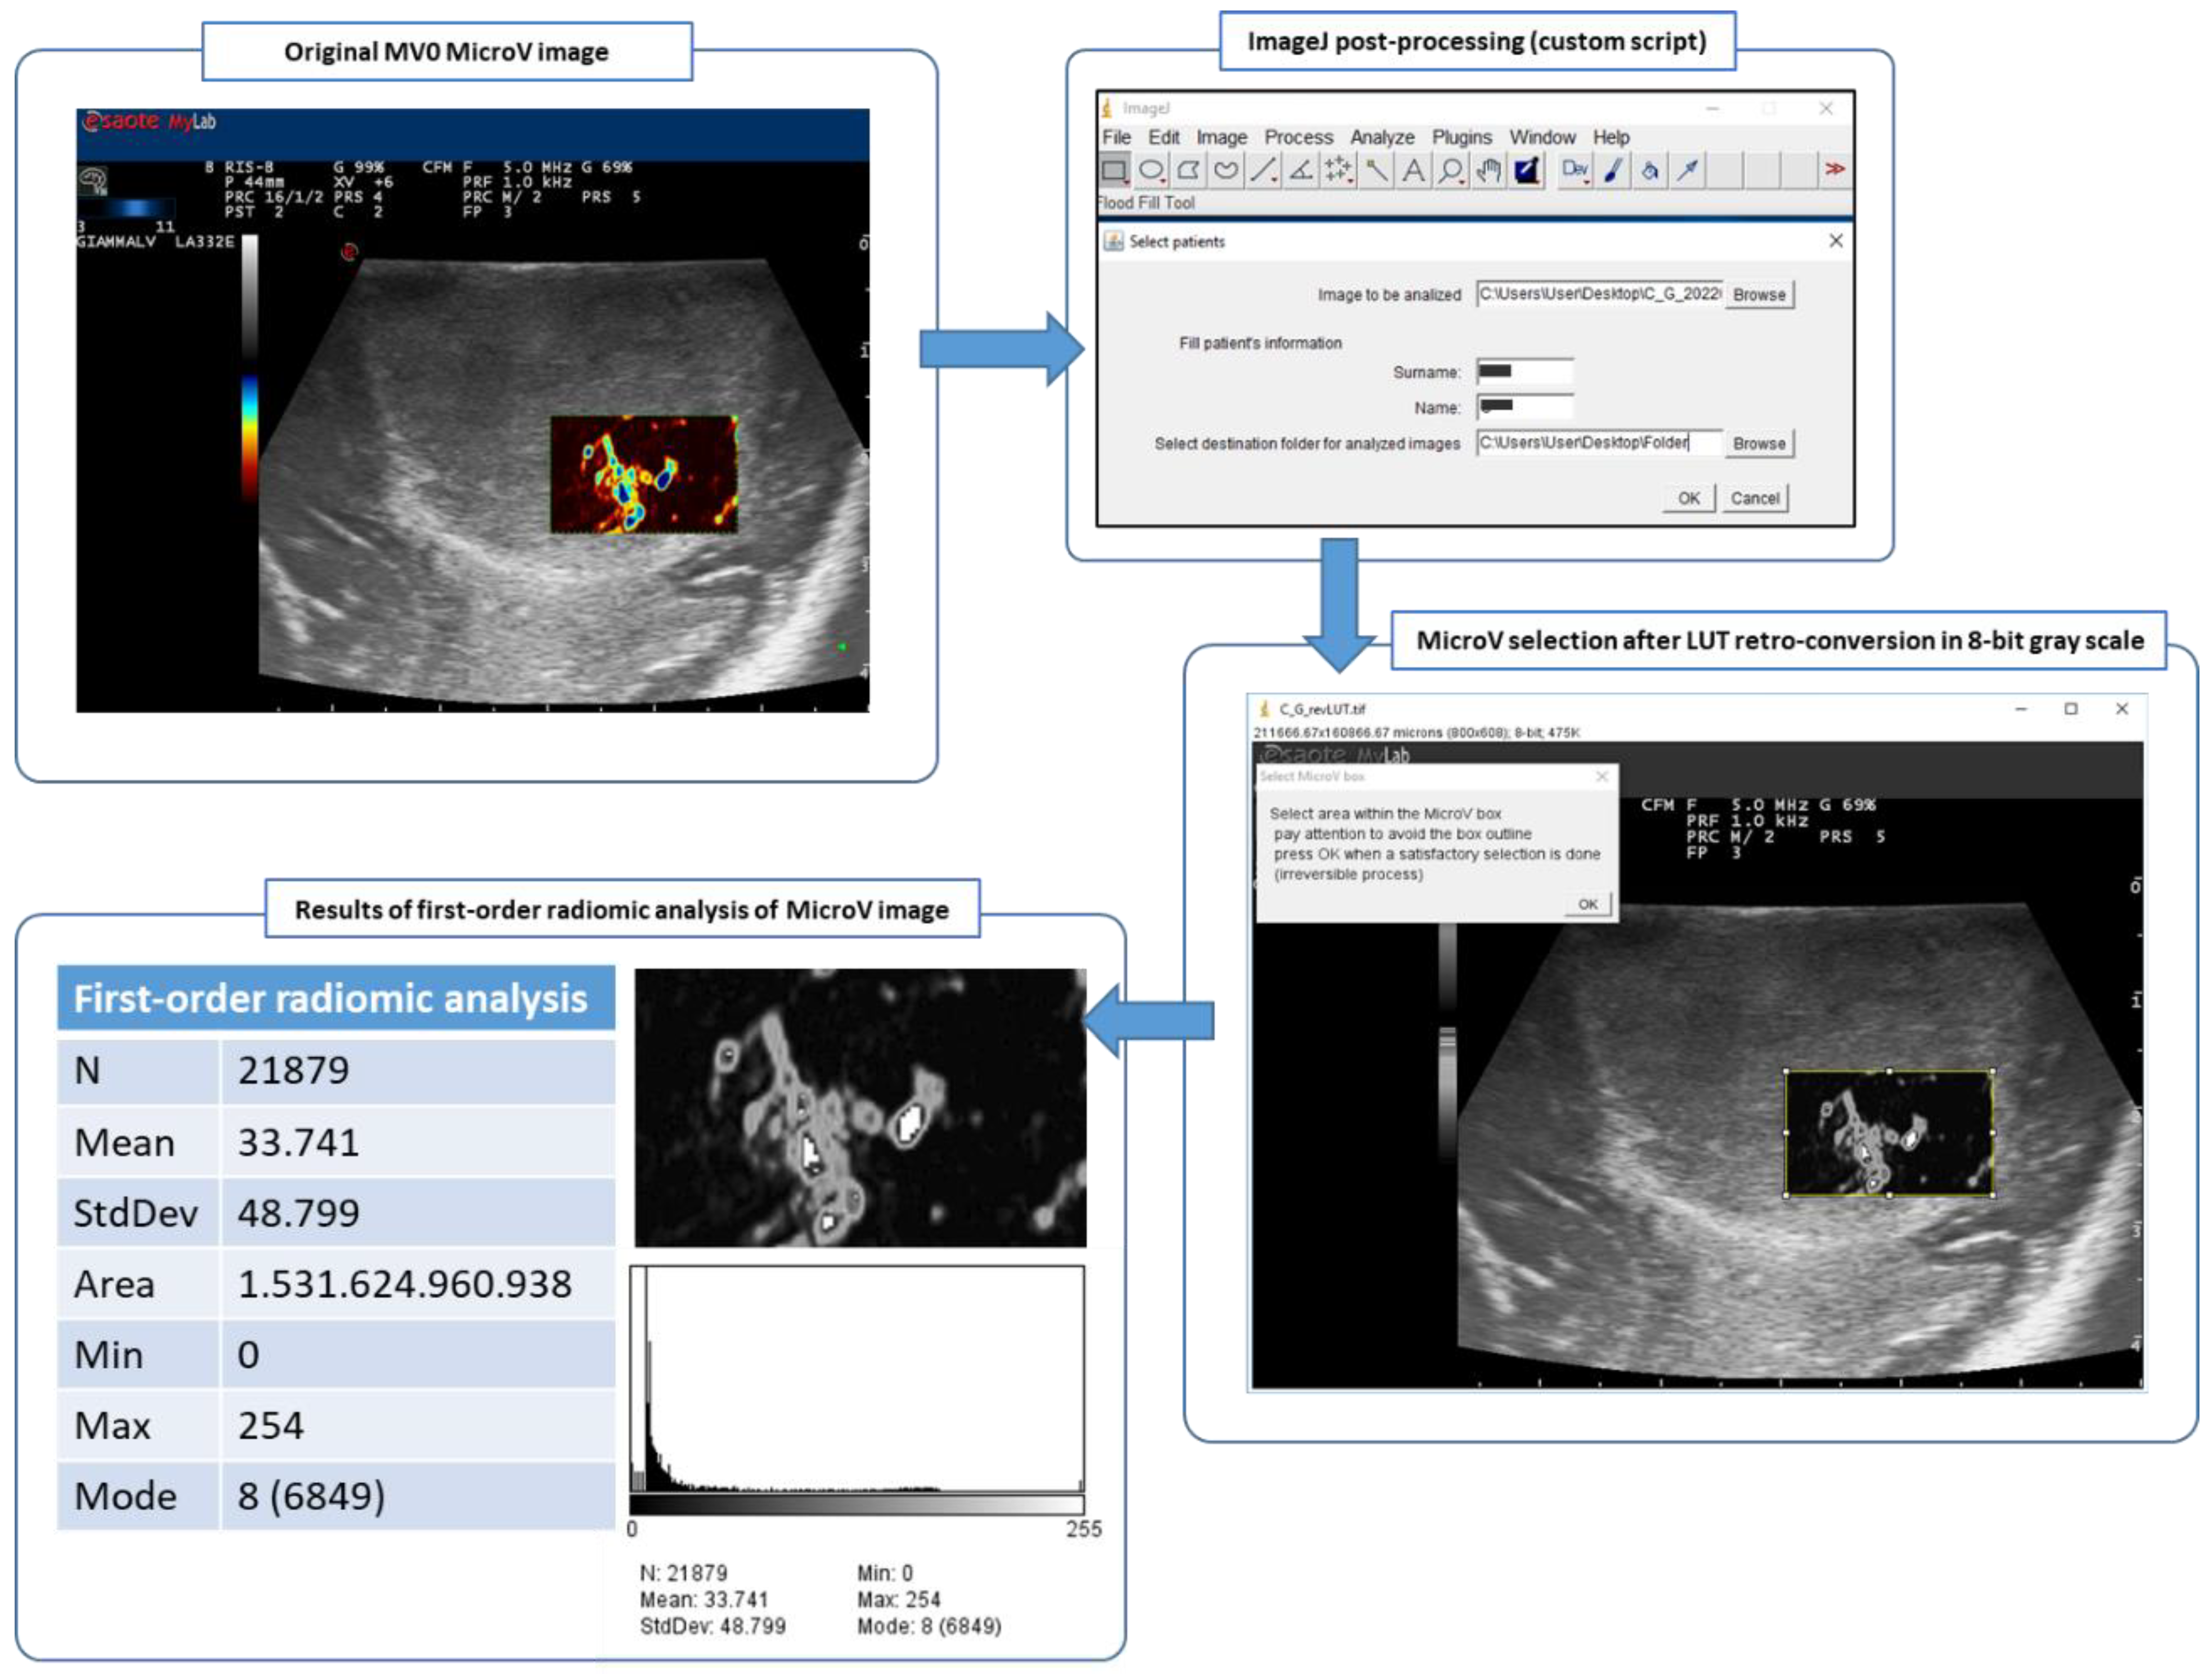

This means that the color-coding related to the flow rates was converted to grayscale, whereby higher flow rates corresponded to higher values of the grayscale and were converted to whiter pixels whereas lower flow rates corresponded to lower values of the grayscale and were converted to blacker pixels (Figure 2).

Figure 2.

Post-processing ImageJ workflow of MicroV IOUS image with MV0 color map, from the original image to the 256 tones 8-bit grayscale image and finally to the first-order radiomic analysis of the selected area within the MicroV box.

2.7.2. First-Order Radiomic Analysis

With an 8-bit grayscale image, the area of the MicroV box was evidenced using a rectangular selection, paying attention to excluding the outline of the box itself.

With intrinsic analyzing tools of ImageJ, the following information were calculated on the selected area: selected area; average, minimum and maximum intensity value of selected pixels; and standard deviation and histogram with quantitative distribution of pixels according to their intensity. In this way, higher values corresponded to faster and more-represented flow rates, whereas lower values corresponded to slower and less-represented flow rates. Distribution of pixels per intensity might represent the pattern of microvascularization.

Numerical data thus obtained were recorded for further analysis and the histogram of pixel distribution were saved in TIFF format (Figure 2).